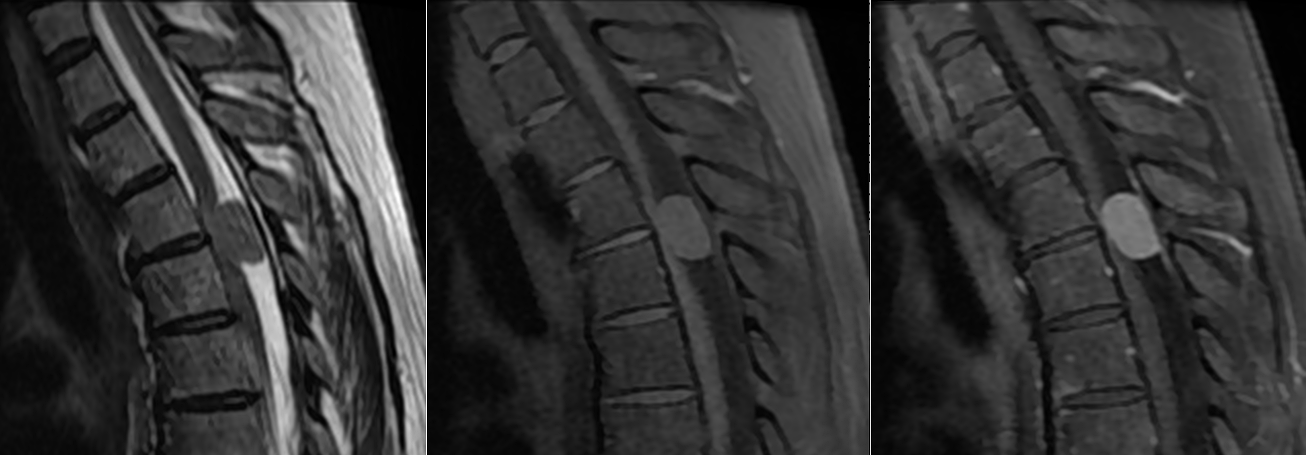

Meningiom spinal cervical C7-T1 – RMN preoperator

Meningiom spinal cervical C7-T1 – RMN postoperator